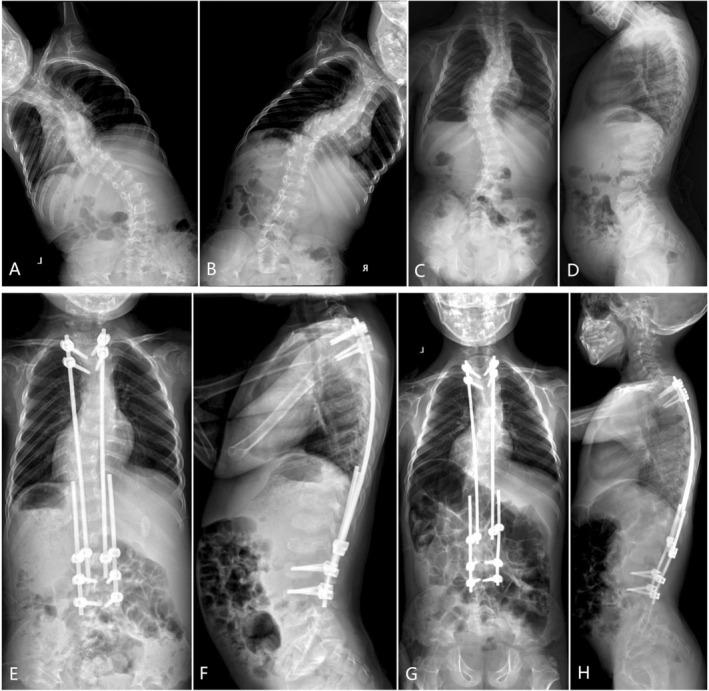

We identified a total of four patients. Patient 1 presented with severe kyphoscoliosis and segmentation defects and received a pedicle subtraction osteotomy with short fusion and dual growing rods from T3 to L3. However, coronal imbalance was observed at the 18-month follow-up. Genetic testing revealed biallelic disease-causing variants in B3GALT6 . A revision surgery was successfully performed, with the level of the LIV extended to the STV (L4). The LIV was similarly extended to the STV in the index surgery for subsequent Patients 2 and 3 who received preoperative genetic testing results, and no complication has been observed. Patient 4 underwent preoperative Halo-pelvic traction to minimize complications, followed by posterior spinal fusion. The curves were successfully reduced without complications. A systematic literature review identified 86 articles reporting (kypho) scoliosis management in 12 of the 63 patients with B3GALT6 -related disorders. Limited surgical experience has been reported, with an increased rate of complications, including death.

我们共确定了4例患者。患者1表现为严重的脊柱后凸侧弯和节段性缺损,接受了经椎弓根截骨术、短节段融合以及从T3至L3的双生长棒植入。然而,在18个月的随访中观察到冠状面失衡。基因检测显示B3GALT6存在双等位基因致病变异。成功进行了翻修手术,将LIV水平扩展至STV(L4)。在随后接受术前基因检测结果的患者2和患者3的初次手术中,LIV同样扩展至STV,且未观察到并发症。患者4在术前进行了头盆牵引以尽量减少并发症,随后进行了后路脊柱融合术。侧弯成功矫正,无并发症发生。系统的文献综述确定了86篇报告,涉及63例B3GALT6相关疾病患者中12例的(后凸)脊柱侧弯治疗。已报道的手术经验有限,并发症发生率增加,包括死亡。